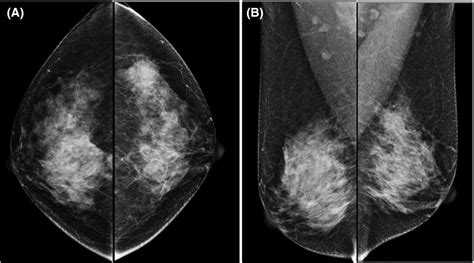

Imaging studies play a critical role in the diagnosis of phyllodes tumors. Common imaging modalities include:

• Mammography: Mammography can detect phyllodes tumors as well-defined, round or oval masses with smooth or lobulated margins. However, it may not always differentiate phyllodes tumors from other breast lesions.

• Ultrasound: Ultrasound provides detailed information about the tumor's size, shape, and internal characteristics. Phyllodes tumors typically appear as solid, hypoechoic masses with well-defined margins.

• Magnetic Resonance Imaging (MRI): MRI offers high-resolution images of the breast tissue and can help differentiate phyllodes tumors from other breast lesions. It is particularly useful for assessing the extent of the tumor and planning surgical intervention.